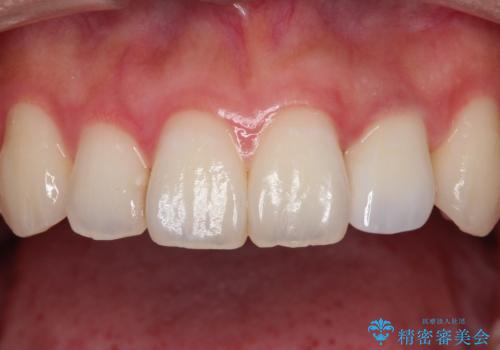

前歯の変色 オールセラミッククラウン

- 前歯の変色を主訴に来院されました。

根管治療後、オールセラミッククラウン(エクセレント)にて治療を行なっています。

オールセラミッククラウン(エクセレント)は、技工士さんが立会う事で色調や形態の相談を行うことができ、満足度の高い治療を行うことができます。